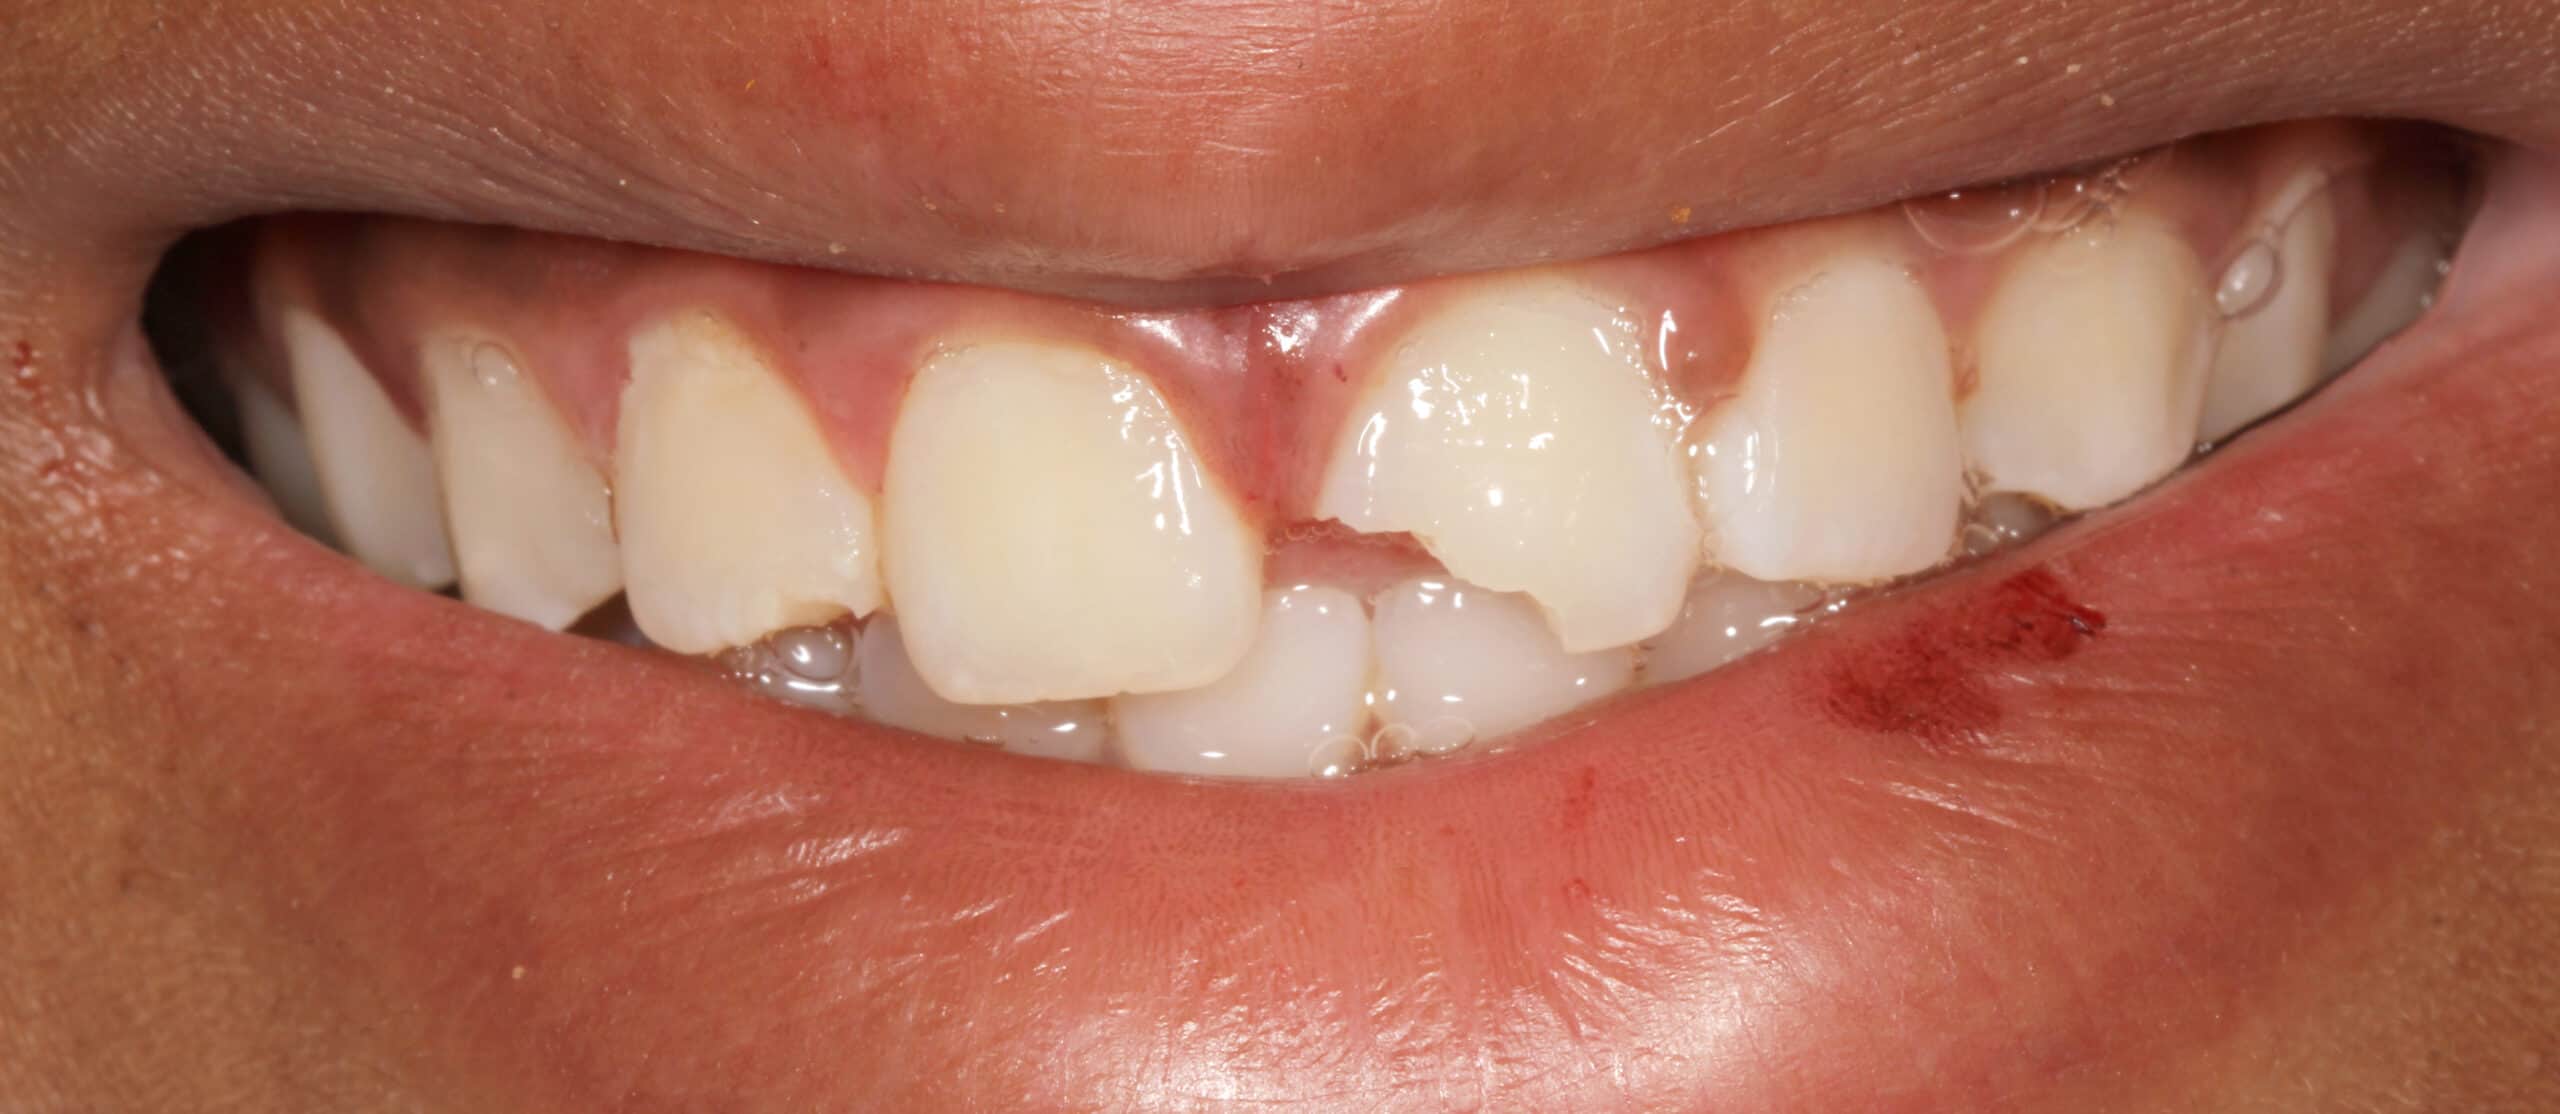

12 year old male patient fell of his bicycle on a Saturday. He hit his lip and front teeth on the pavement. He did not have much tooth pain after the initial trauma. He presented the next day to our office to evaluate the tooth for repair. As an emergency dentist in NYC we treat all types of tooth injuries.

Luckily, his front tooth did not suffer any nerve damage. The tooth was not mobile and mostly intact aside from the obvious fracture. The nerve in the tooth is was healthy, not causing any significant pain.

Since the front tooth did not sustain any nerve damage it was safe to proceed with restoring the tooth with a bonding. A bonding is the same material we often use in dental fillings. We usually do not place porcelain veneers or crowns on patients under 17 years old. Since, young patients’ bone is still growing, the crown may not look correct a few years after placement.

In this case we decided to restore the tooth with dental bonding or filling material. The procedure was performed chair-side in our office with a bit of anesthesia since the tooth was still sensitive from the trauma that it suffered. Patient left our office very happy.